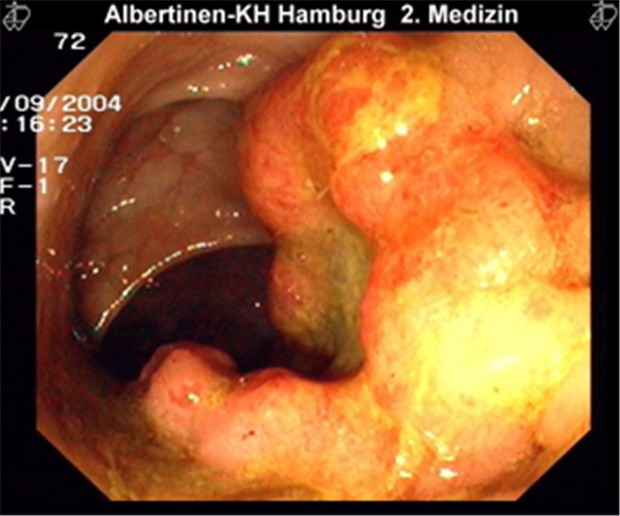

Großes Rektum-Ca.

© Albertinen-KH / endoskopiebilder.de